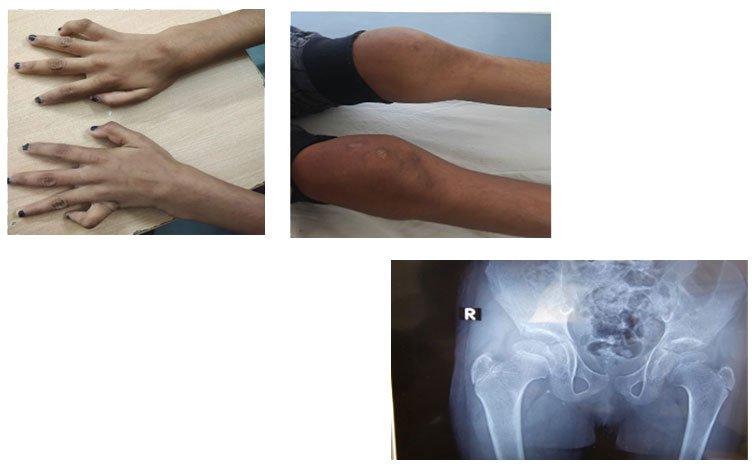

A 9-year-old girl, born of a consanguineous marriage, presented with progressive finger flexion deformities and swelling of wrists, knees, and ankles since age four. She was previously diagnosed with polyarticular JIA and treated with multiple DMARDs and biologics without response. Re-evaluation at our centre revealed non-inflammatory joint swelling, camptodactyly, restricted movements without tenderness, and radiologic coxa vara.

Answer: Genetic analysis identified a homozygous PRG4 c.619del (p.Arg207GlufsTer13) variant, confirming Camptodactyly–Arthropathy–Coxa Vara–Pericarditis (CACP) syndrome. This case explains the importance of distinguishing non-inflammatory arthropathy from JIA, especially in refractory cases with atypical pain.